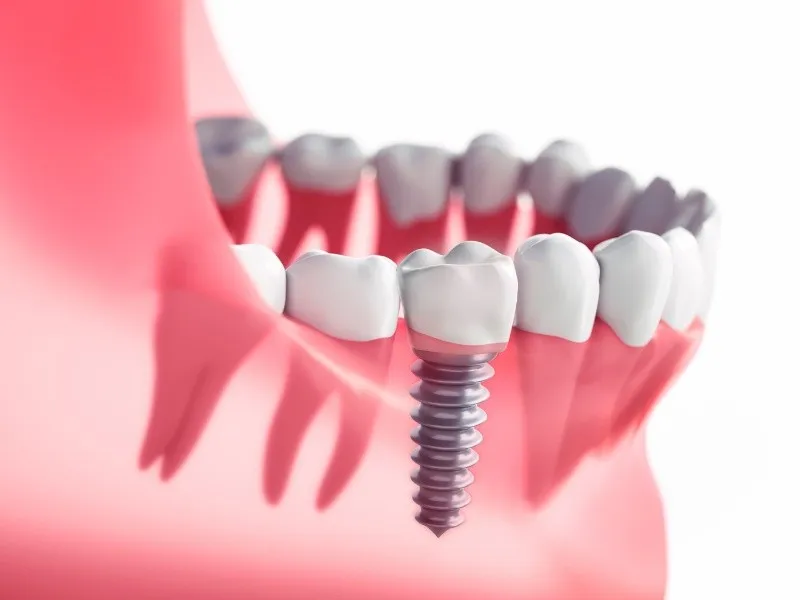

Bước 3: Đặt trụ Implant

Bác sĩ sẽ tiến hành gắn trụ Implant vào xương hàm. Tạo thành chiếc chân răng “nhân tạo” chắc chắn cho mọi người. Nếu cấy nhiều trụ implant hoặc thực hiện phẫu thuật ghép xương, nâng xoang, nong xương… thì cần 2-3 ngày nghỉ dưỡng. Nếu cấy ghép Implant đơn lẻ thì bạn có thể sinh hoạt bình thường hay sau khi gắn trụ.